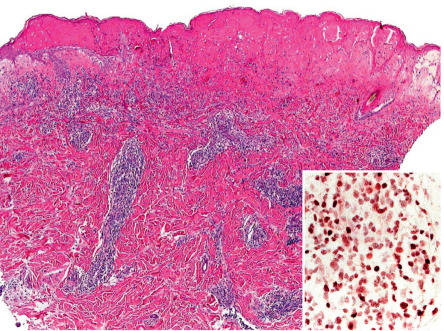

Pathology

There is epidermal spongiosis and acanthosis, lymphocytic exocytosis, and a superficial and deep, often dense, perivascular lymphohistiocytic dermal cellular infiltrate, often containing eosinophils and plasma cells . In more severely affected skin, erosions, focal epidermal necrosis, Pautrier microabscess-like epidermal cellular collections, dermal–epidermal junction fibrin deposition, dermal neutrophils with nuclear dust, vertically streaked papillary dermal collagen, and/or small, multinucleated dermal giant cells are often seen; in addition, the dense infiltrate, epidermal lymphocyte exocytosis, and frequent nuclear polymorphism may on occasion suggest a histologic diagnosis of cutaneous T-cell lymphoma (CTCL).